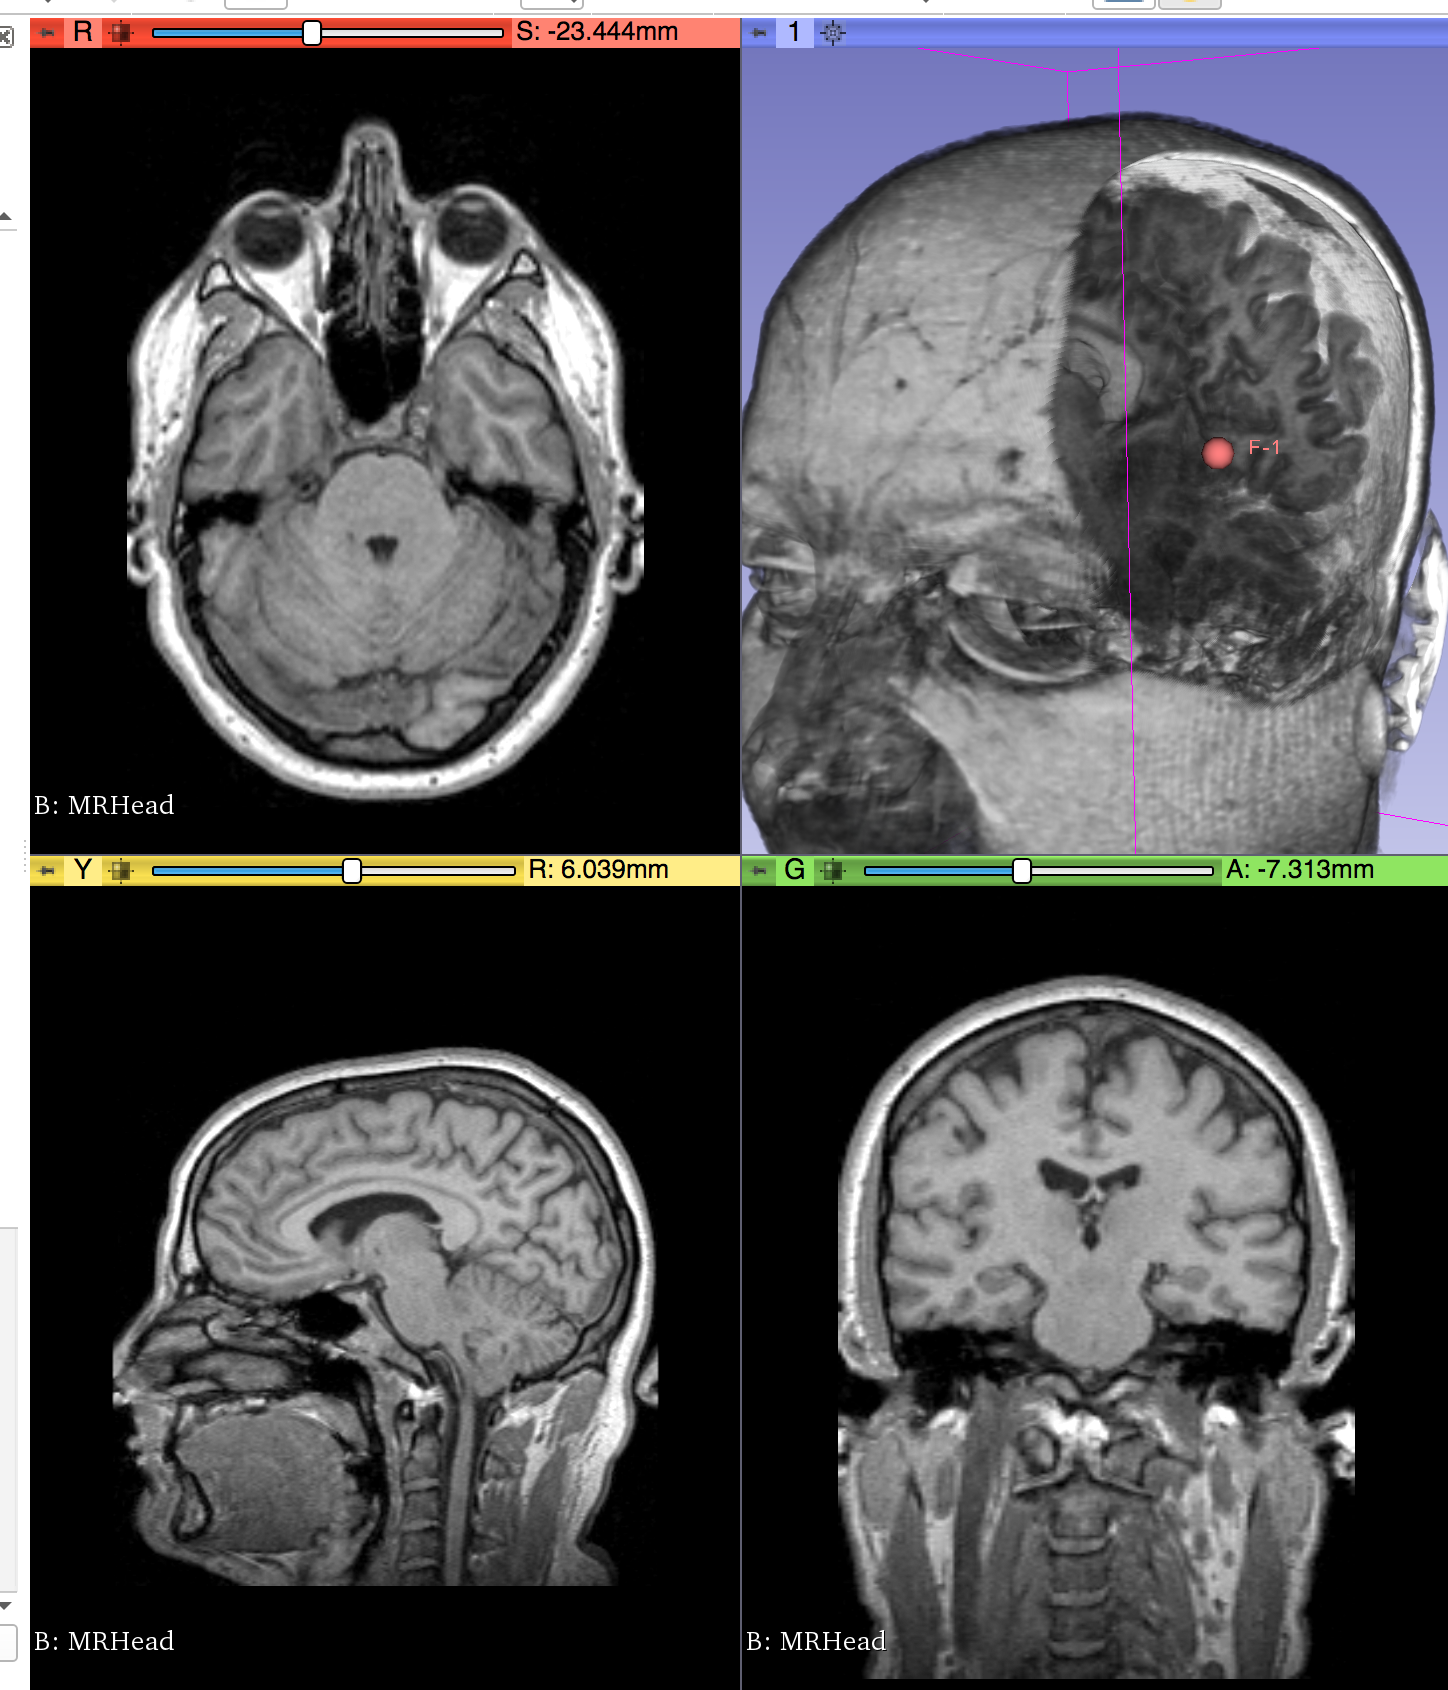

| Philips 3D US | Chroma-depth in PRISM | Depth peeling in PRISM |

|---|---|---|

![]() |

| Edge enhancement in PRISM | Decluttering in PRISM | Volume carving in PRISM |